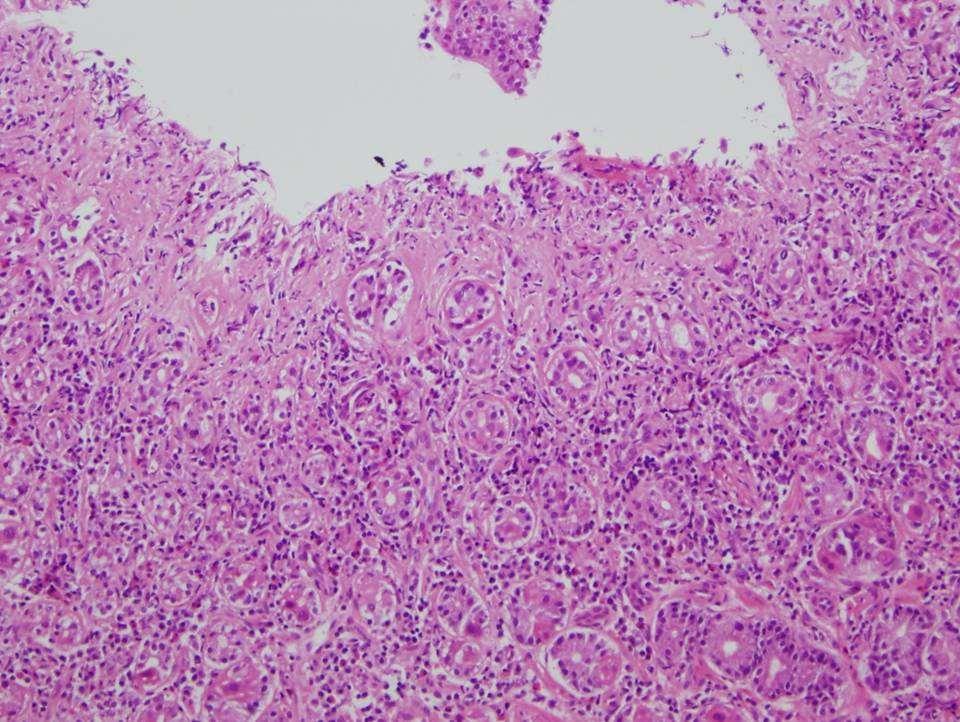

• 2. A 64 year old female with antral ulceration and thickening: The biopsy shows individual and small clusters of atypical cells in the lamina propria. The cells have abundant vacuolated cytoplasm with peripheral enlarged nuclei. The cytoplasm is Alcian blue - PAS positive.

•.K Answer

• Causes

• Classification (gross & histologic)

• Staging

• Gastric dysplasia